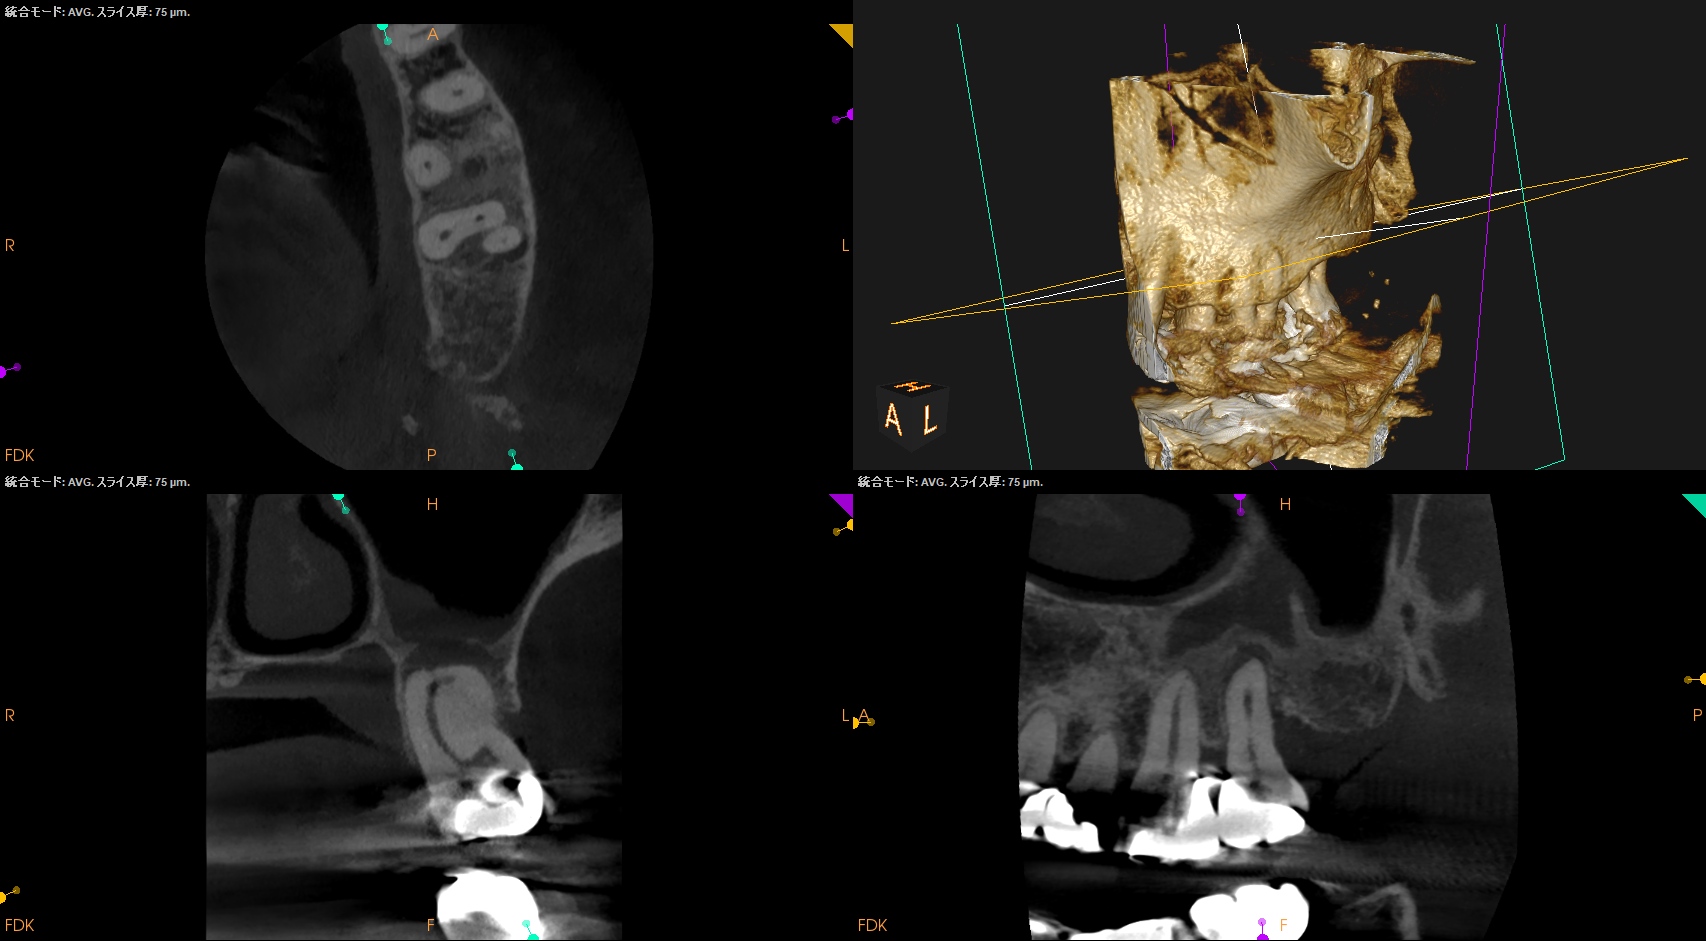

CBCT(2024.7.31)

MB

DB

P

根尖病変があり、上顎洞炎を呈している。

根管治療が必要だ。

Pre-op Endo Diagnosis(2024.7.31)

Pulp Dx: Pulp Necrosis

Periapical Dx: Symptomatic apical periodontitis

Recommended Tx: RCT